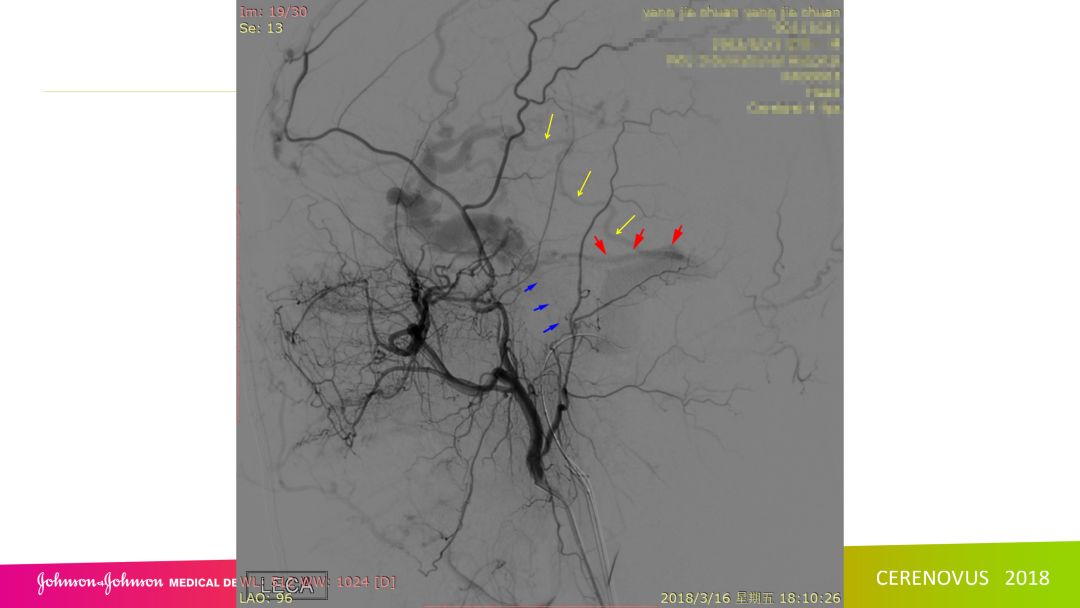

复合手术治疗海绵窦区硬脑膜动静脉瘘一例